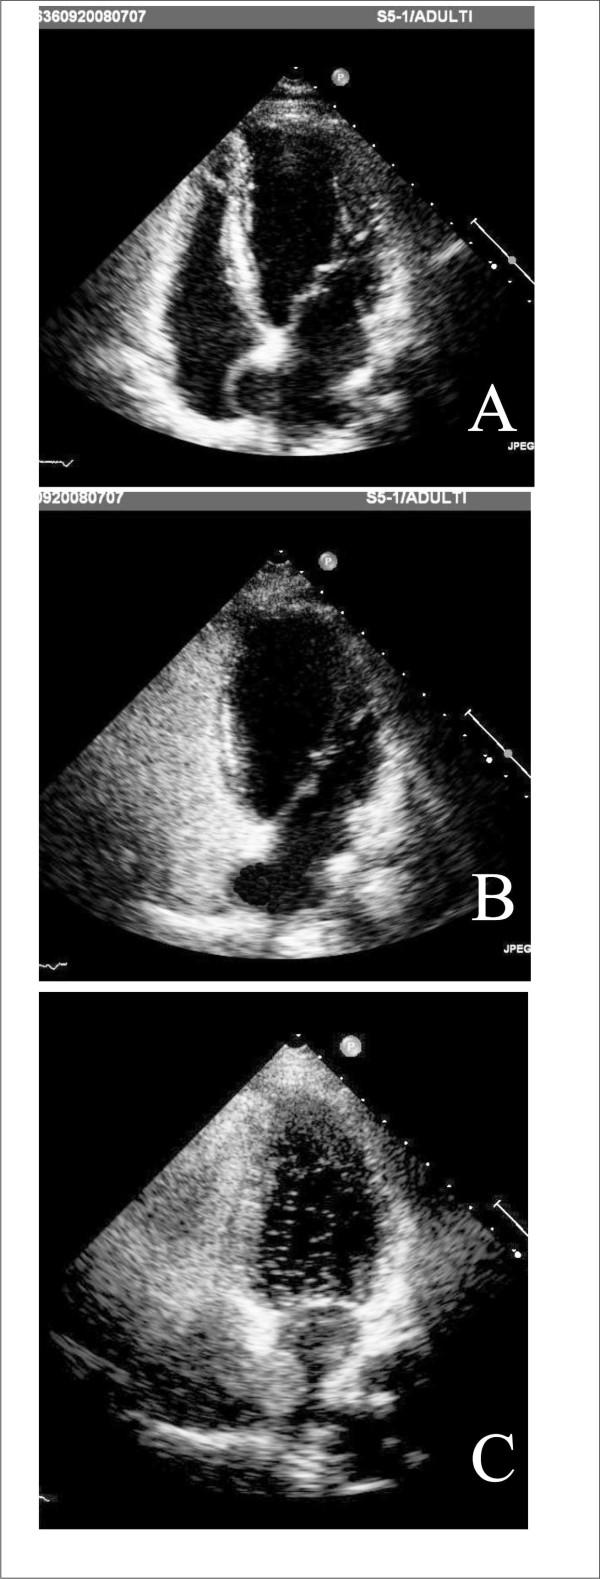

Aortic stenosis and mitral regurgitation, patent foramen ovale, interatrial septal defect, atrial fibrillation and perivalvular leak, are now amenable to percutaneous treatment. These percutaneous procedures require the use of Transthoracic (TTE), Transesophageal (TEE) and/or Intracardiac echocardiography (ICE). This paper provides an overview of the different percutaneous interventions, trying to provide a systematic and comprehensive approach for selection, guidance and follow-up of patients undergoing these procedures, illustrating the key role of 2D echocardiography.

主动脉瓣狭窄、二尖瓣反流、卵圆孔未闭、房间隔缺损、心房颤动及瓣周漏,目前均适合经皮治疗。这些经皮手术需要使用经胸超声心动图(TTE)、经食管超声心动图(TEE)和/或心内超声心动图(ICE)。本文概述了不同的经皮介入治疗,试图为接受这些手术的患者提供一种系统、全面的选择、指导及随访方法,并阐述二维超声心动图的关键作用。